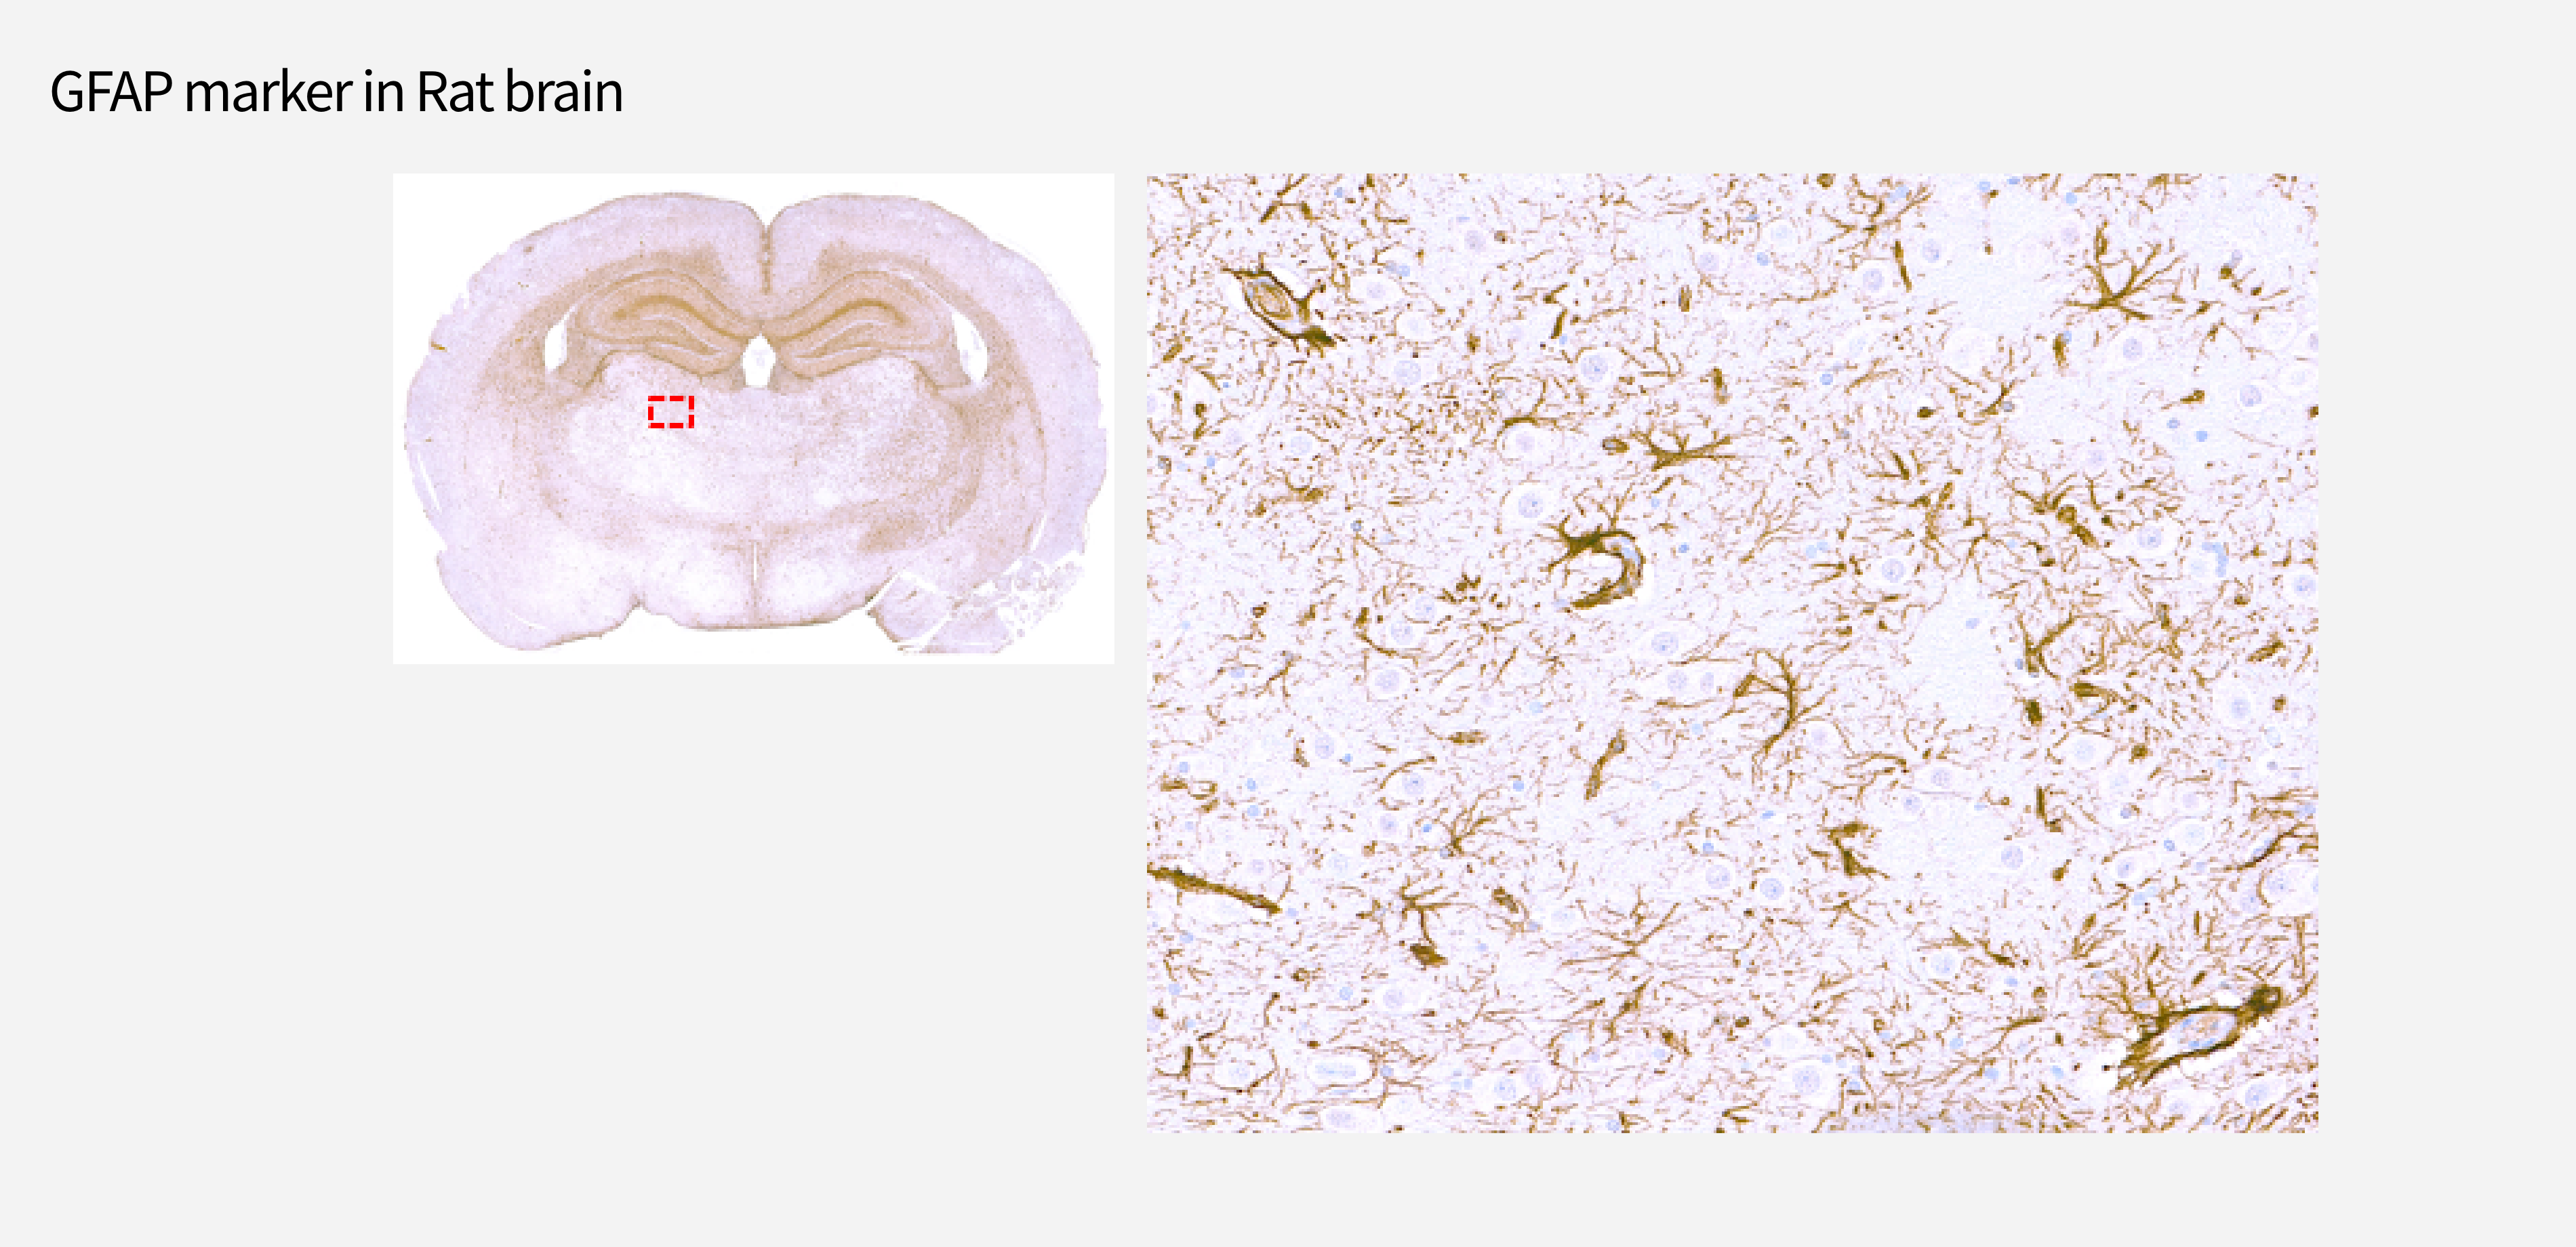

Implant 체결 구조 분석

Resin 제작

비탈회

(레진제작)

Implant

3D printed lumbar cage

Coronary stent

Polymer